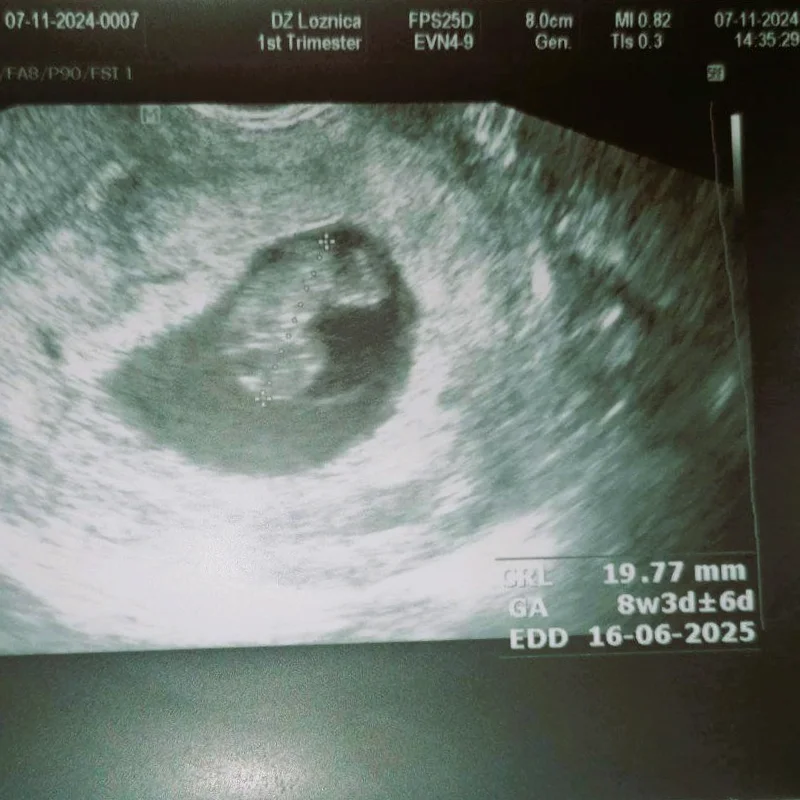

završavamo 2024. godinu s ogromnim ponosom i radošću! Ove godine naša zajednička borba donela je 5 predivnih beba i još jednu trudnoću na putu! ❤️👶